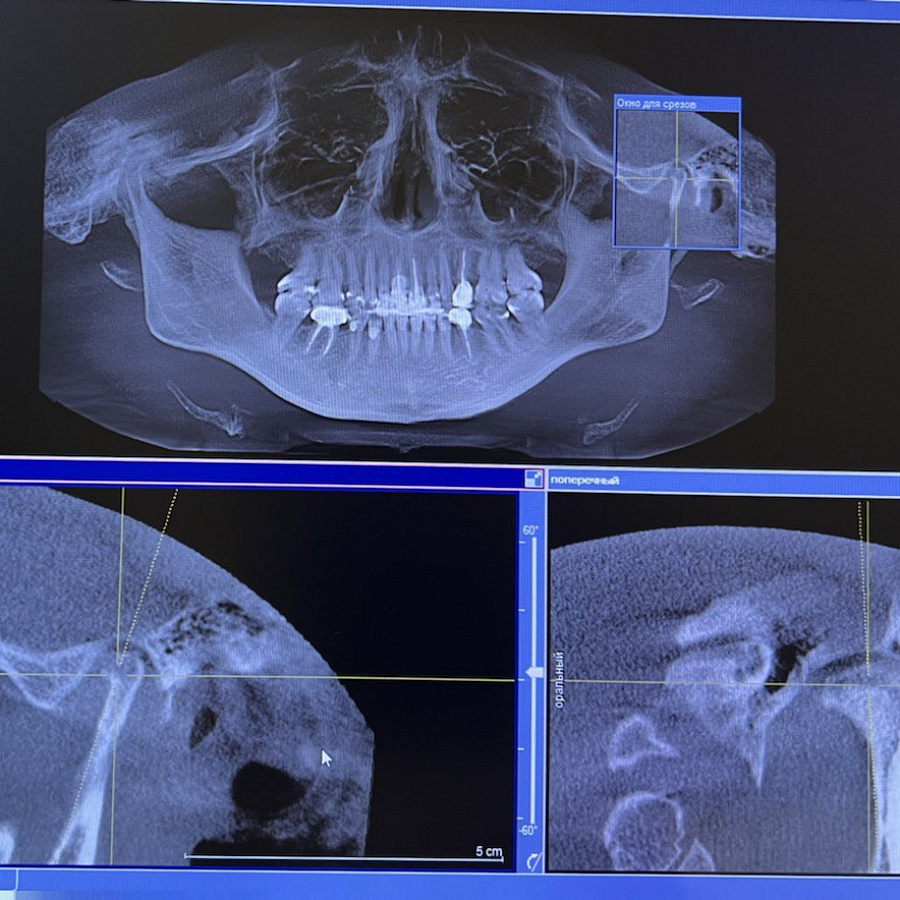

Боль в шее, щелчки в суставе и ограничения открывания рта, панические атаки, нарушение дыхания, искривление осанки.

Работали ортодонт-гнатолог и ортопед-гнатолог. Установили ортотик, изменился контур подбородка, выровнялся прикус, ушли все боли и трудности с челюстью и дыханием, исчезли панические атаки.